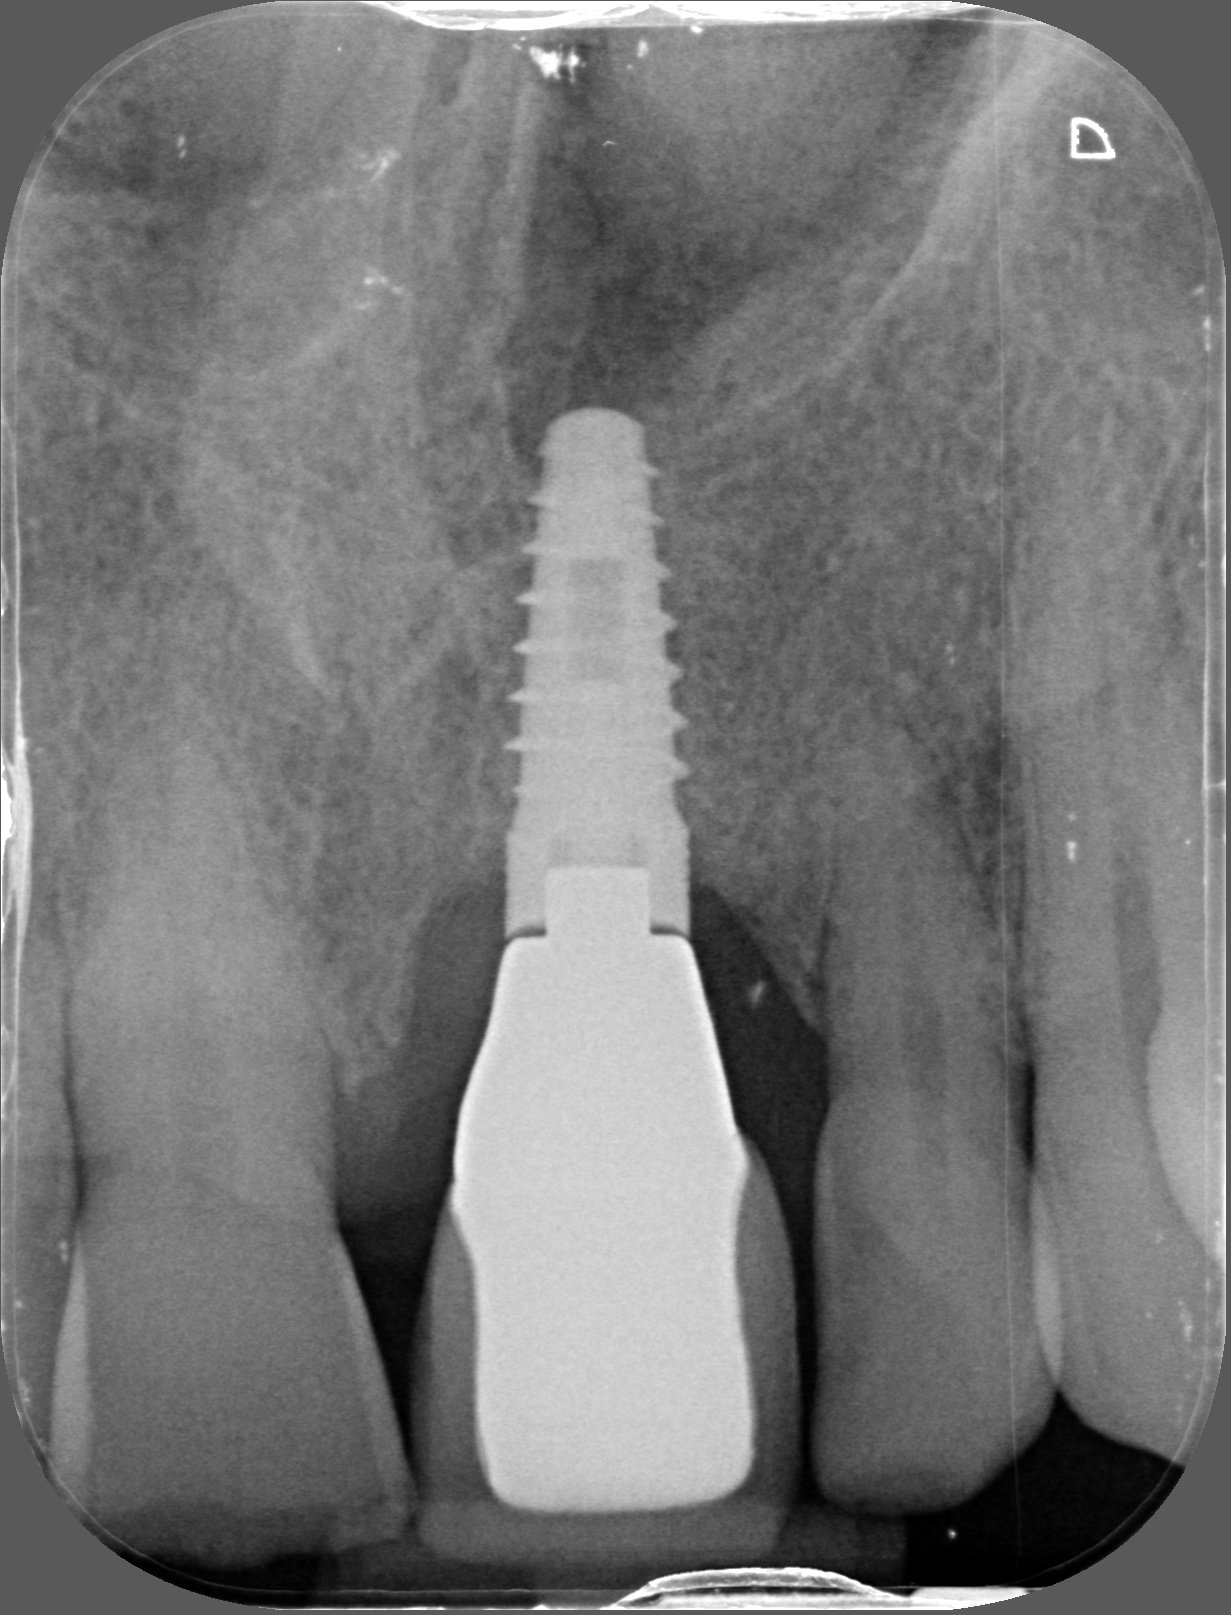

Implante en el central, es conexion interna

Hola, me gustaria saber que implante lleva este paciente en el central, tengo que rehabilitarlo, muchas grcaias de antemano.